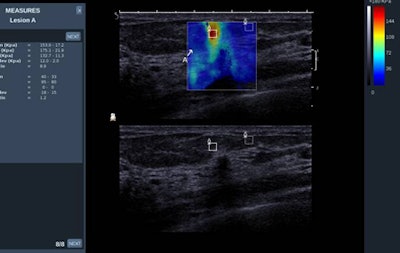

Ultrasound elastography has been around since the 1980s and emerged as a complementary technique to estimate local tissue stiffness. There are two main types: strain imaging (externally applied compression using the probe and creating a local tissue deformation) and shear-wave imaging (no external compression, shear-wave emission, and propagation through the tissue is responsible for local tissue displacement). Its utility has already been established for use in liver cirrhosis, as well as breast, prostate, and thyroid lesions.

"Breast elastography is indeed helpful in providing further information about breast lesion stiffness, the point being that cancers are stiffer than benign lesions and lesions having a similar B-mode aspect could be further differentiated as benign or malignant according to their stiffness (i.e., their elastic value)," noted Dr. Alexandra Athanasiou, from the radiology department at the Institut Curie in Paris.

Strain elastography provides qualitative or semiquantitative information, whereas shear-wave imaging provides quantitative values of elasticity and is more operator-independent, she explained.